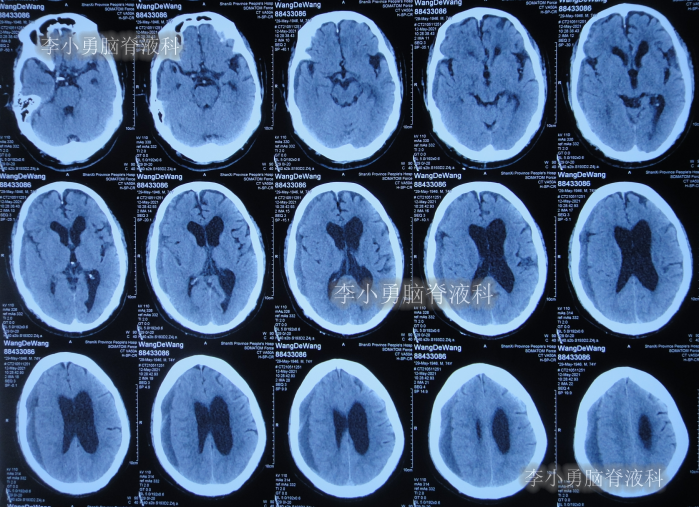

2020年10月29日(发病已8年),因症状一直没有得到改善且呈进行性加重趋势,查头部核磁示脑积水(图-1)。

图-1:2020年10月29日头部核磁

发现脑积水后8天即2020年11月6日,就诊于第2家的上海的某三甲医院,入院后再次检查(图-2)后诊断为正常压力脑积水。

图-2:2020年11月11日头部核磁